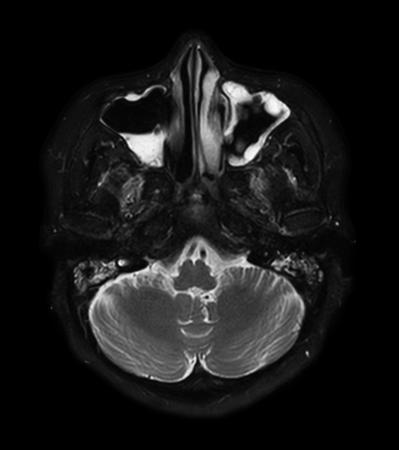

Axial mDIXON XD - T2w TSE (Water only)